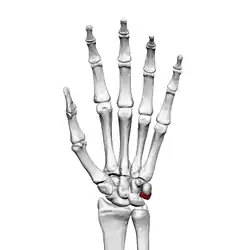

![]() Left hand anterior view (palmar view). Triquetral bone shown in red. | |

The triquetral bone (/traɪˈkwɛtrəl, -ˈkwiː-/; also called triquetrum, pyramidal, three-faced, and formerly cuneiform bone) is located in the wrist on the medial side of the proximal row of the carpus between the lunate and pisiform bones. It is on the ulnar side of the hand, but does not directly articulate with the ulna. Instead, it is connected to and articulates with the ulna through the Triangular fibrocartilage disc[1] and ligament, which forms part of the ulnocarpal joint capsule.[2] It connects with the pisiform, hamate, and lunate bones. It is the 2nd most commonly fractured carpal bone.

The triquetral is one of the eight carpal bones of the hand. It is a three-faced bone found within the proximal row of carpal bones. Situated beneath the pisiform, it is one of the carpal bones that form the carpal arch, within which lies the carpal tunnel. [3]: 708

The triquetral bone may be distinguished by its pyramidal shape, and by an oval isolated facet for articulation with the pisiform bone. It is situated at the upper and ulnar side of the carpus. To facilitate its palpation in an exam, the hand must be radially deviated so that the triquetrium moves out from under the ulnar styloid process. The triquetrum may be difficult to find, since it also lies under the pisiform.